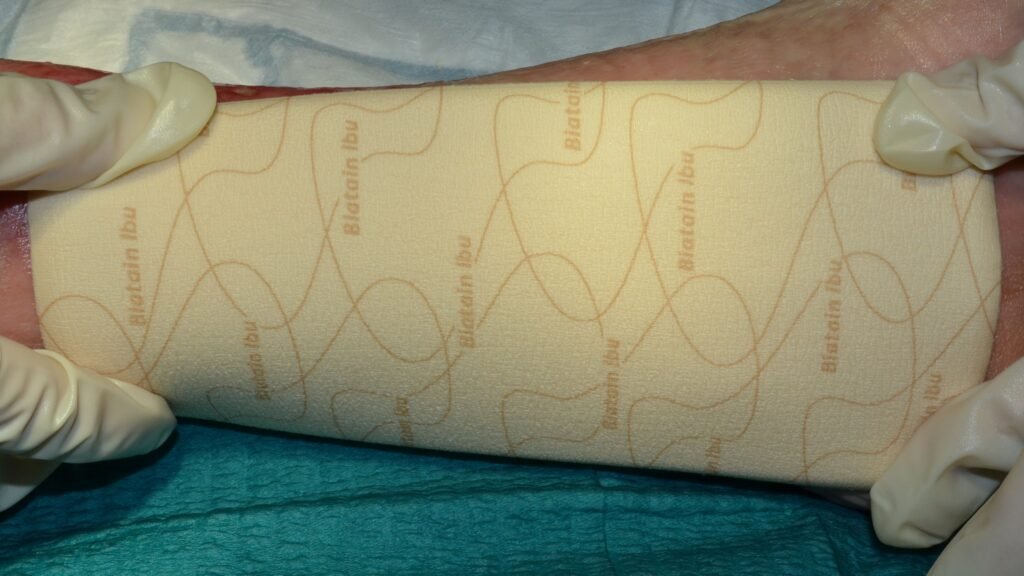

Biatain Ibu Schaumverband nicht-haftend

Biatain Ibu Schaumverband sanft-haftend